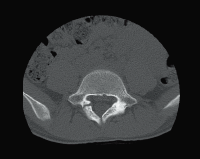

Клинические изображения

Для снижения лучевой нагрузки и повышения качества визуализации в КТ SUPRIA используются алгоритм интеллектуального перераспределения дозы IntelliEC и современный метод итерации IntelliIP, позволяющие провести сканирование с очень низкими значениями доз и получить изображения необходимого диагностического качества. В результате лучевая нагрузка на исследуемую область существенно снижается при сохранении высокого качества визуализации, особенно на уровне плотных паренхиматозных органов.